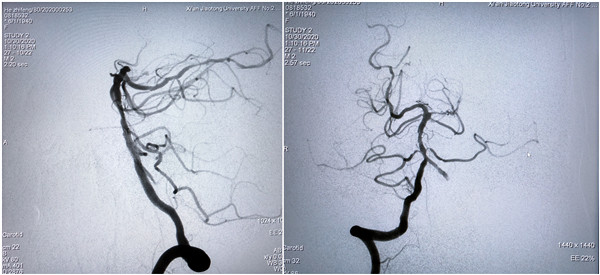

术中北京天坛医院神经介入科莫大鹏教授、中国医科大学第四附属医院神内高连波教授通过远程直播平台实时点评,对此次直播的手术难度、技术细节等进行点评、交流。历经一个多小时,手术顺利完成,圆满取得预期效果。此次直播利用我院新引进的西门子双C臂血管造影机,充分展示了新型血管造影机在神经介入方面的优势,展示了我院神经内科规范、先进的介入治疗方式和技巧。